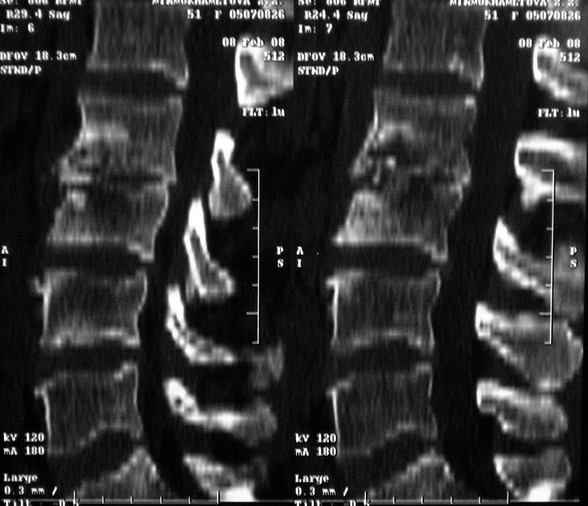

Re: Требуется телеконсультация Вертебролога

MRI через три недели